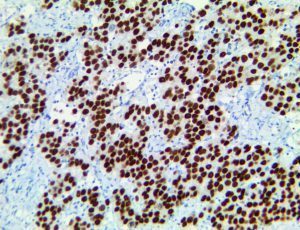

It is the ICU physician who is most likely to witness one of the deadliest manifestations of the abnormal immunological response, the cytokine storm syndrome (CSS). This response is also referred to by some as the cytokine release syndrome (CRS). CSS is characterized by continuous activation and expansion of macrophage and lymphocyte populations, which secrete large amounts of cytokines, causing the cytokine storm. This massive cytokine release is akin to hemophagocytic lymphohistiocytosis (HLH) disease, a syndrome characterized by initial unchecked and persistent activation of cytotoxic T lymphocytes and NK cells.

Clinical and laboratory manifestations of HLH include fever, enlarged liver and/or spleen, neurologic dysfunction, coagulopathy, liver dysfunction, cytopenias (i.e., low levels of erythrocytes, leukocytes, and/or platelets), hypertriglyceridemia, hyperferritinemia, hemophagocytosis, and eventually diminished NK cell activity as the immune system becomes progressively paralyzed. HLH can be familial (primary HLH) or secondary to another disease process (sHLH), such as rheumatic disease, in which it is referred to as macrophage activation syndrome (MAS, characterized by elevated ferritin).